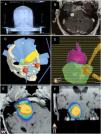

Material and methodsThis retrospective descriptive study included 64 patients treated from 2010 to 2016 with a minimum follow-up of one year, excluding patients with neurofibromatosis. Clinical–radiological parameters were evaluated. The treatment was performed using LINAC-RS. The prescribed dose was 12Gy at 90% isodose.

ResultsThe mean age at treatment was 53 years, 56% were women. Ninety-eight percent of the patients had hearing loss, 71% with grade III according to the Gardner–Robertson Classification. The mean volume at treatment was 2.92cc and the mean follow-up, 40.95 months. The overall therapeutic success was 90%, reaching 100% at 12 and 24 months, and 86% after 36 months of follow-up. The radiological result was significantly related to the initial tumour volume (p<0.037). In 20 patients there was evidence of transient tumour growth compatible with pseudoprogression. Acute complications were present in 37.5%, and transitory complications in 50%. Chronic complications were found in 20%, with 84% being permanent. The rate of acute complications was lower in patients with regression (p<0.016). Chronic complications were more frequent in the 41–60 year old age group (p<0.040).